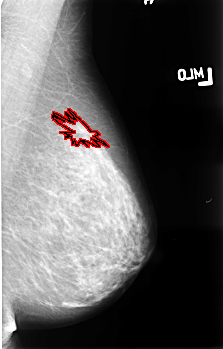

FILE: B_3477_1.LEFT_MLO.OVERLAY

TOTAL_ABNORMALITIES 1

ABNORMALITY 1

LESION_TYPE MASS SHAPE ARCHITECTURAL_DISTORTION MARGINS ILL_DEFINED-SPICULATED

ASSESSMENT 4

SUBTLETY 3

PATHOLOGY MALIGNANT

TOTAL_OUTLINES 1

BOUNDARY